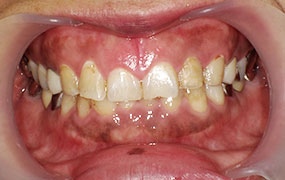

- 歯肉を電気メスで切除する事によって笑った時に歯が見える症状(ガミースマイル)を改善する事を目的とした治療です。

- 治療前

| 治療名(症例) | 歯肉整形(ガミースマイル) |

|---|---|

| 症例 | ガミースマイル |

| 治療本数 | 8本 |

| 治療期間(通院回数) | 1日(2回) |

| 費用 | 4万円+TAX |

| リスク副作用 | ・切除した歯茎が後戻りする可能性があります。 ・術後2週間程は赤みや微出血が生じる場合があります。 ・2~3日は麻酔をした部分が内出血となって、しみたり痛みを伴う場合があります。 |